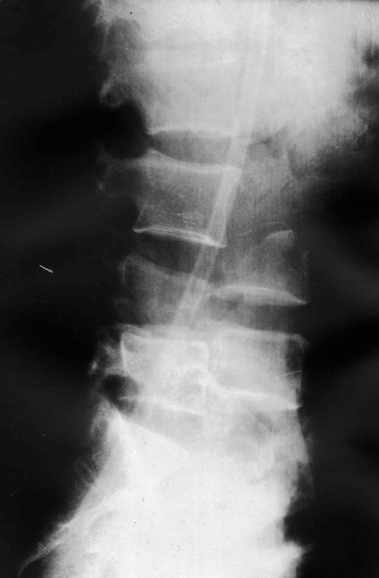

Поступил мужчина 37 лет. Автотравма - перевернулся на машине.

При поступлении состояние тяжёлое. Диагноз: "Оскольчатый перелом тела L3 позвонка, переломы корней дуг L3, l4 позвонков, дислокация (птоз) тел l3, L4 позвонков, множественные флотирующие переломы рёбер слева, гемопневматоракс". При всём при этом практически никакой неврологической симптоматики (легкое онемение по наружной поверхности левого бедра) функции тазовых органов не нарушены, движения в нижних конечностях сохранены. КТ сделать нет технической возможности, сканы рентгенограмм плохого качества поэтому высылаю скиаграммы. Рентгенограммы пришлю позже. Встало два вопроса: Теоретический - как грамотно сформулировать диагноз позвоночной травмы? Практический - тактика оперативного лечения позвоночной травмы. В настоящий момент сосстояние пациента стабилизировалось. С уважением Андрей Стасюк

1

Высылаю рентгенограммы. Спасибо за рекомендации. Наша тактика согласуется с вашими рекомендациями за исключением транспедикулярной фиксации - у данного пациента на наш взгляд предпочтительнее наружная транспедикулярная фиксация (Курганский аппарат). Погружная конструкция предпологает одномоментную репозицию до выполнения забрюшинного доступа и ревизии переломов что теоретически может привести к повреждению дурального мешка и корешков. АВФ позволит восстановить ось позвоночника и смещение по длине непосредственно под контролем глаза на этапе внебрюшинного доступа. Сколько сегментов замыкать? Я думаю может потребоваться замкнуть и сегмент L2-L3. Предполагается использовать тело L4 для костной пластики таким образом, чтобы ширина спиномозгового канала на уровне оперированных сегментов была увеличена. Фиксация тел позвонков вентральной пластиной.